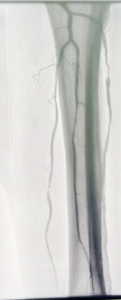

Ocurre cuando hay un estrechamiento de los vasos sanguíneos fuera del corazón. La causa más frecuente de esta enfermedad es la ateroesclerosis.